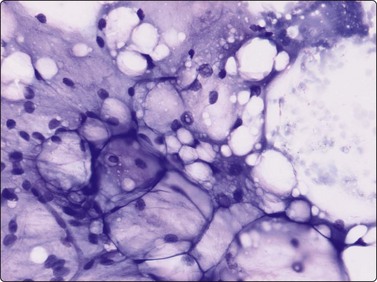

Smears of spindle cell lipoma may have a background of fibromyxoid ground substance and a variable number of spindle cells within tissue fragments or between them. (Fig. 15.20A). The spindle cells may dominate the smears and may be misinterpreted as a fibroblastic proliferation. Important diagnostic features in FNB smears from spindle lipoma are the presence of hyaline, eosinophilic collagen fibers (Fig. 15.20B) and of mast cells. The spindle cells stain strongly for CD34 (Fig. 15.21). The cytological appearance of spindle cell lipoma in smears have been described in a series of 12 cases.36 Pleomorphic lipoma, considered to be related to spindle cell lipoma (similar typical site and chromosomal aberration) typically displays so-called floret cells in smears (Figs 15.22). In a typical clinical setting (a subcutaneous tumor in the neck or back in a middle-aged male), a confident diagnosis of both these variants of lipoma is possible. Hibernoma is recognisable in FNB smears provided that typical hibernoma cells are found. These have abundant, finely granular or vacuolated cytoplasm and centrally located small, rounded uniform nuclei (Fig. 15.23).37 The typical findings in FNB smears of lipoblastoma (subcutaneous) and lipoblastomatosis (deep-seated) are a vascular network and clusters of lipoblast-like cells in a myxoid background (Fig. 15.24). Another variant of benign lipoma, chondroid lipoma, has been described. In this variant foci of mature adipocytes are seen together with chondrocyte- or lipoblast-like cells in a chondromyxoid-like matrix.38 The cytomorphology of chondroid lipoma has so far been described only in single case report.39,40 The main features are lipoblast-like cells with irregular nuclei, often lobulated or coffee-bean shaped, mixed with mature fat cells within fragments of a chondroid-like matrix (Fig. 15.25). Chondroid lipoma has been erroneously diagnosed as low-grade malignant liposarcoma (paucicellular myxoid liposarcoma) in FNB samples. Extra-adrenal myelolipoma is a tumor-like mass composed of mature fat and bone marrow cells. The typical site is the adrenals but the lesion can also occur in the retroperitoneum and in the pelvic region. Extra-adrenal myelolipoma should be considered in the differential diagnosis of tumors or tumor-like lesions in those sites. FNB smears typically contain fragments or clusters of normal fat cells mixed with bone marrow cells of all three lineages (Fig.15.26).

Myxoid liposarcoma, the commonest of the liposarcomas is currently divided in two variants: paucicellular and hypercellular myxoid liposarcoma. Paucicellular myxoid liposarcoma is identical with the classic myxoid liposarcoma, while the hypercellular variant corresponds to the former round cell liposarcoma. The reason to rename round cell liposarcoma is that this subtype was found to express the same chromosomal aberration, t(12;16)(q13;p11), as classic myxoid liposarcoma.10 In paucicellular myxoid liposarcoma, the peculiar network of anastomosing capillary vessels is well recognisable in FNB smears and is one of three characteristic features. The other two are abundant myxoid background matrix and slightly atypical lipoblasts. Smears consist mainly of small tissue fragments with branching capillary vessels embedded in the myxoid matrix (Fig. 15.28A). The tumor cells, mainly seen in the fragments, have spindle or ovoid, relatively uniform nuclei and a thin cytoplasm. Lipoblasts are always found – uni- or multivacuolated with scalloped nuclei (Fig. 15.28B). The lipoblasts are best visualised in MGG; the cytoplasmic vacuoles are less prominent in H&E. Differentiation from low-grade malignant myxofibrosarcoma (MFS) depends on the demonstration of the capillary network within the tumor fragments and of lipoblasts. The vessel fragments seen in smears of MFS are usually thicker and are present in the myxoid ground substance. Smears of hypercellular myxoid liposarcoma (former round cell liposarcoma) show either numerous dissociated cells or tissue fragments containing closely packed tumor cells. The fragments are considerably more cellular than those of the paucicellular type; myxoid ground substance is less conspicuous and the capillary network less prominent. The tumor cells have irregular, rounded nuclei and a malignant chromatin pattern. The cytoplasm is fragile and many nuclei are stripped. Mitotic figures are occasionally seen and atypical lipoblasts always found.

image image

Fig. 15.28 Myxoid liposarcoma

(A) Tissue fragment of cells embedded in myxoid background material; typical anastomosing vessels (MGG, IP); (B) Scattered multivacuolated lipoblasts (MGG, HP).